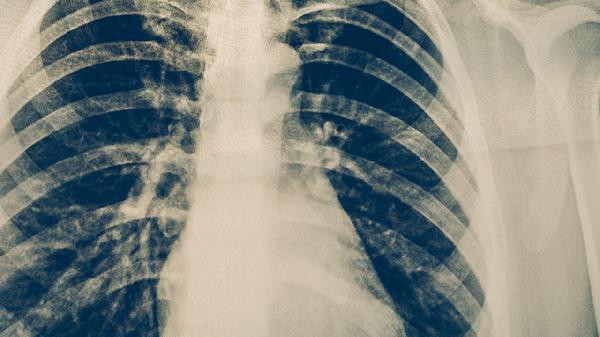

肺结核药物治疗

肺结核药物治疗通常需要遵医嘱使用异烟肼片、利福平胶囊、吡嗪酰胺片、乙胺丁醇片、链霉素注射液等抗结核药物。肺结核是由结核分枝杆菌感染引起的慢性传染病,药物治疗需遵循早期、联合、适量、规律、全程的原则。

肺结核患者除规范用药外,需保证充足营养摄入,多吃高蛋白食物如鸡蛋、瘦肉、豆制品等。适当进行散步、太极拳等温和运动有助于增强体质。治疗期间应严格戒烟戒酒,保持居住环境通风良好。定期复查胸部影像学和痰菌检查,全程完成6-9个月的治疗周期。出现药物不良反应应及时就医调整方案,不可自行停药或更改剂量。密切接触者应进行结核菌素试验筛查。